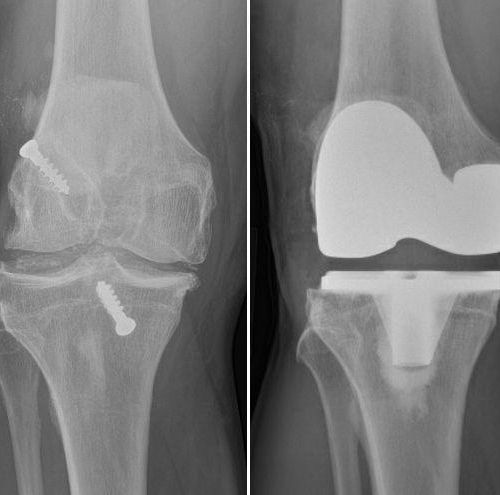

JOINT REPLACEMENT / ARTHOPLASTY

Advanced knee arthritis – left image,

Total knee replacement – right image